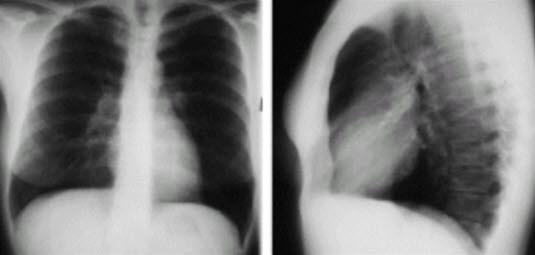

Røntgenbilde av lunger med blodproppDiagnosen kan noen ganger være vanskelig å stille i tidlig fase eller ved små blodpropper. Vanlige symptomer på blodpropp i lungene er:

Diagnosen kan være vanskelig å stille. Mistanke om lungeemboli på grunnlag av sykehistorien fører alltid til akutt innleggelse på sykehus. Der vil det bli tatt blodprøver, blant annet for å påvise eller utelukke andre sykdommer som kunne medført disse plagene. Lungene vil bli grundig undersøkt, og en spesiell CT-undersøkelse av blodårene i lungene kan gi sikkert svar.